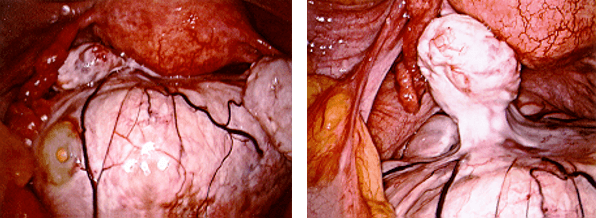

The photos below show several different types of ovarian masses:

Left photo – a tumor arising from the right ovary. Middle photo – a closeup of the ovarian mass, which was an ovarian fibroma (a benign solid ovarian tumor). Right photo – taken after the fibroma had been removed by laparoscopy.